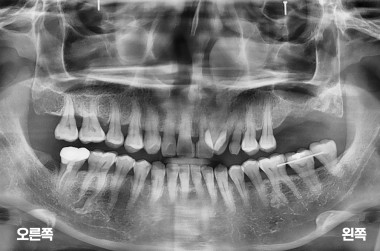

상악동 거상술 및 왼쪽 윗 어금니 두개 임플란트 수술